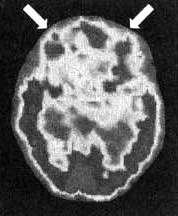

Результаты сканирования SPECT у Сэлли

Снимок в горизонтальной плоскости — мозг в состоянии покоя. Обратите внимание на хороший уровень активности в префронтальной области (отмечено стрелками).

Снимок в горизонтальной плоскости во время концентрации. Обратите внимание на выраженное снижение активности, особенно в префронтальной коре.